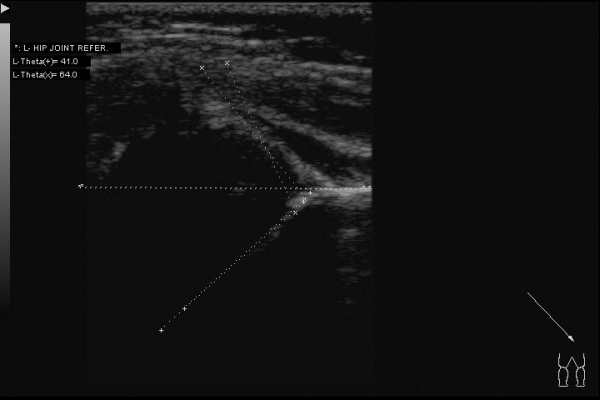

Доброго всем дня. Интересный случай сегодня: клинически у ребенка (2,5 месяца) все нормально -- отведение в полном объеме, ротация -- норма. Складки -- симметрия. Но!!! В анамнезе у мамы ребенка врожденный вывих бедра. Решил выполнить УЗИ:

Таким образом видим полное соответствие УЗИ картины -- рентгенограмме.